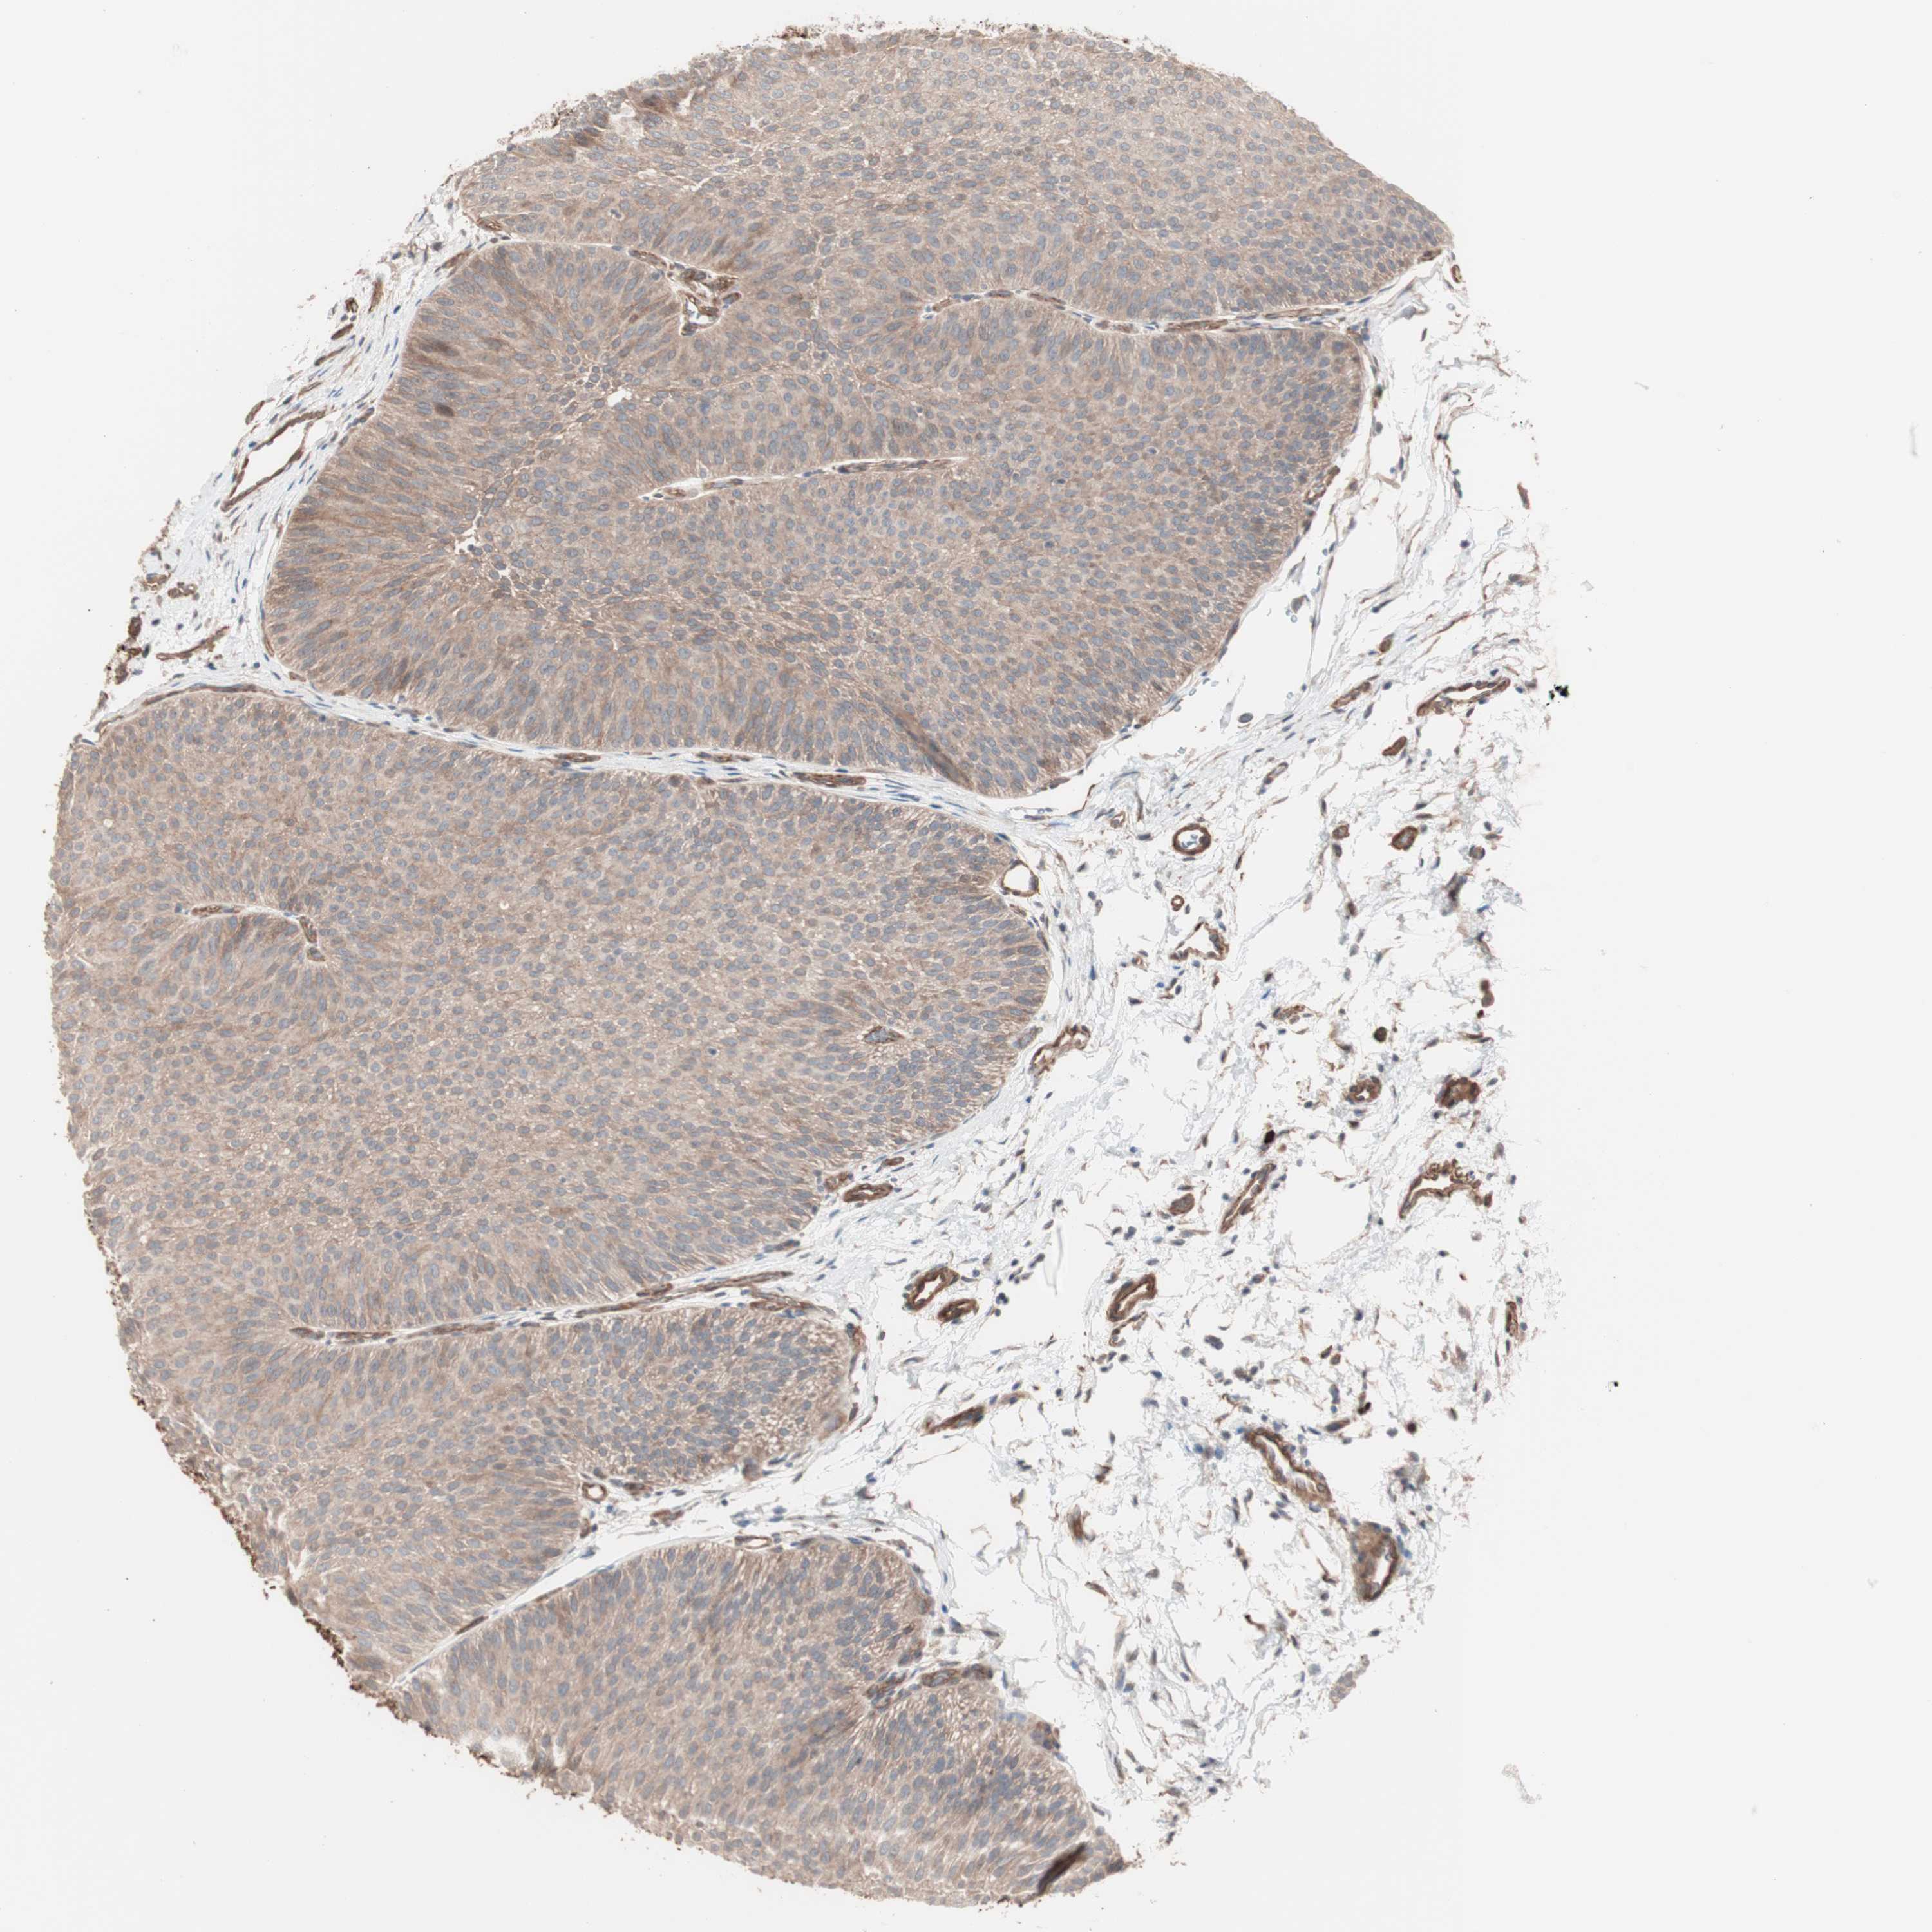

UROTHELIAL CANCER - Protein expressioni

A mouse-over function shows sample information and annotation data. Click on an image to view it in a full screen mode. Samples can be filtered based on level of antibody staining by selecting one or several of the following categories: high, medium, low and not detected. The assay and annotation is described here.

Note that samples used for immunohistochemistry by the Human Protein Atlas do not correspond to samples in the TCGA dataset.

Antibody stainingi

Antibody staining in the annotated cell types in the current human tissue is reported as not detected, low, medium, or high, based on conventional immunohistochemistry profiling in selected tissues. This score is based on the combination of the staining intensity and fraction of stained cells.

Each image is clickable and will lead to virtual microscopy that enables deeper exploration of all samples and also displays staining intensity scores, fraction scores and subcellular localization as well as patient and tissue information for each sample.

Antibody HPA007989

Staining

High

Medium

Low

Not detected

Intensity

Strong

Moderate

Weak

Negative

Quantity

>75%

75%-25%

<25%

None

Location

Nuclear

Cytoplasmic/membranous

Cytoplasmic/membranous,nuclear

Urothelial carcinoma, Low grade

Urothelial carcinoma, High grade